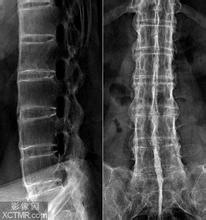

二、放射线片诊断:除了通过疾病的症状进行诊断外,大家也可采用该方法诊断疾病。放射线片可表示强直性脊柱炎 早期关节四面有斑片状骨质疏松区,骶髂关节的中下段最为明显,病情逐渐加重可出现骨腐蚀与软骨下骨皮质硬化,关节 间隙狭小,甚至骶髂关节融合强直。强直性脊柱炎发病后,椎间盘、脊椎小关节、肋脊关节,后纵韧带与寰枢关节也会出 现不同程度的炎症、反应性骨硬化、邻近椎体腐蚀、椎体变形等症状,终极脊柱完全融合。